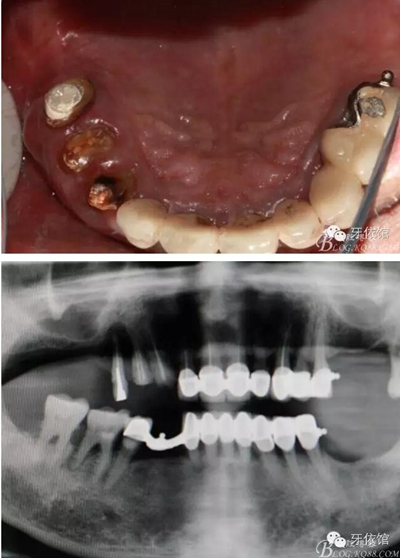

患者男,64歲,左上6,7、右上6,7缺失,6年前做上頜球帽附著體,前幾日右上3,4,5烤瓷牙脫落,右上3,4冠折,右上5三度松動。x光示根尖周大面積陰影。